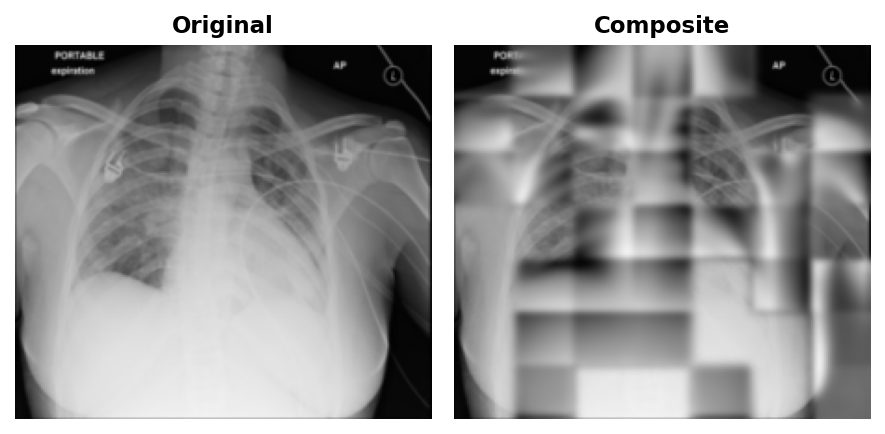

To visualise what the network was learning, the model is run on val images and its predictions are composited back onto the originals. First, the model predicts in per-patch-normalised space, so predictions are re-scaled using the mean and standard deviation of the visible pixels to put all patches on the same brightness reference frame. Second, the composite feathers the edges with a Gaussian blur.

At epoch 50, blurry outlines were visible in the reconstructions.

By epoch 100, coarse lung field boundaries and rib cage structure were visible in the reconstructions.

By epoch 199, finer details like individual rib edges and lung vasculature emerged.

No matter what epoch, the patches will always be visible. This is a direct consequence of patchwise normalisation: the loss normalises each 32x32 patch to zero mean and unit variance independently before computing MSE. Adjacent predicted patches have slightly different overall exposure, and there is nothing in the loss to penalise that mismatch at the boundary, nor should it.